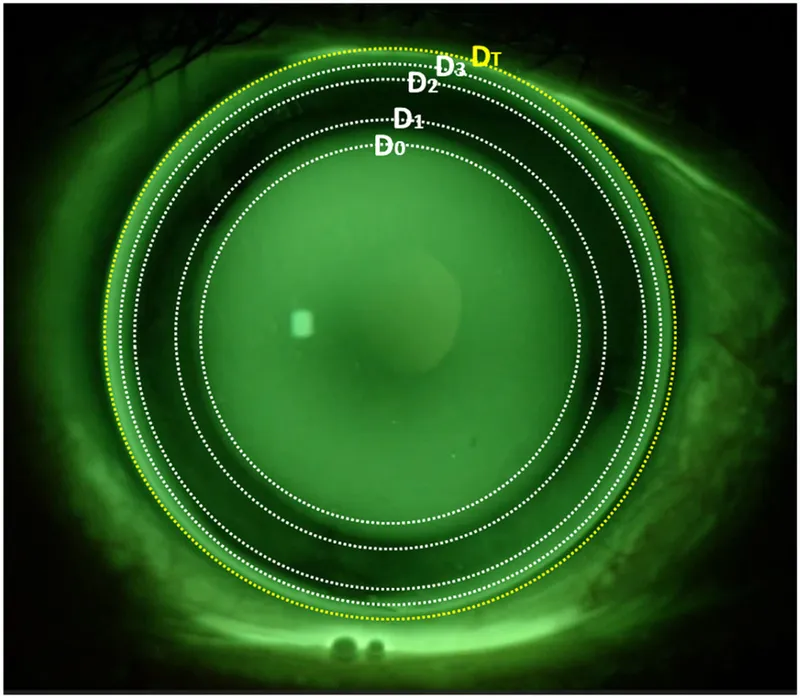

Fluorescein Patterns:

- Alignment: Even, thin green layer; slight ↑ peripheral clearance.

- Steep Fit: Central pooling (deep green); minimal edge lift. (Too tight)

- Flat Fit: Central touch/bearing (dark); excessive peripheral pooling/edge lift. (Too loose)

⭐ An ideal RGP fit shows good centration, adequate movement (1-2mm post-blink), and an even, thin layer of fluorescein under the optic zone.